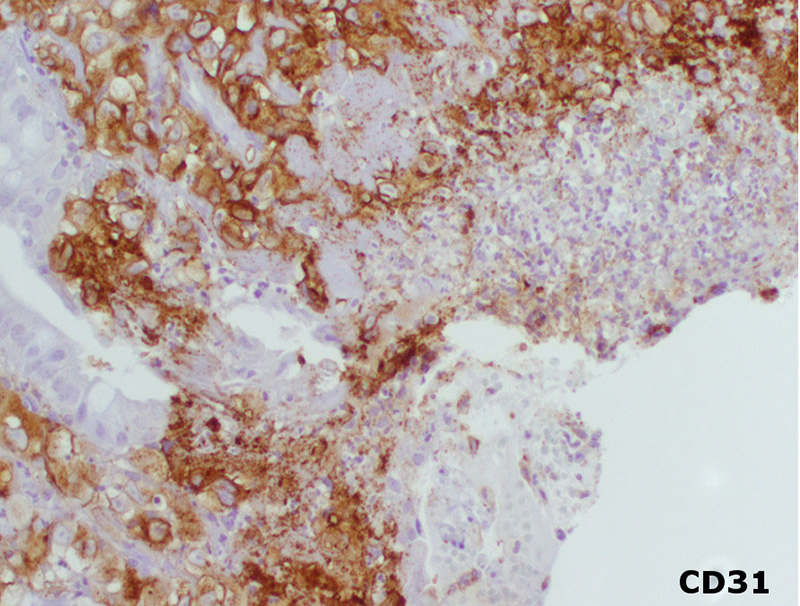

Imaging studies (computed tomography scan of the abdomen and chest radiograph) did not reveal a source for the bleeding or a mass lesion. The EGD demonstrated multiple red-brown polypoid masses within the stomach and duodenum (Figure 1).The biopsies, of both the stomach and duodenum, demonstrated large cells with amphophilic cytoplasm and irregular nuclei with vesicular chromatin and prominent nucleoli infiltrating the lamina propria (Figures 2 and 3). There was subtle vasoformation and, notably, no overlying dysplasia was identified. The neoplastic cells were positive for pan-cytokeratin, cytokeratin 7 (Figure 4), CD31 (Figure 5), and CD34. The neoplastic cells were negative for CDX2, TTF-1, S-100 protein, cytokeratin 20, cytokeratin 5/6, and calretinin.